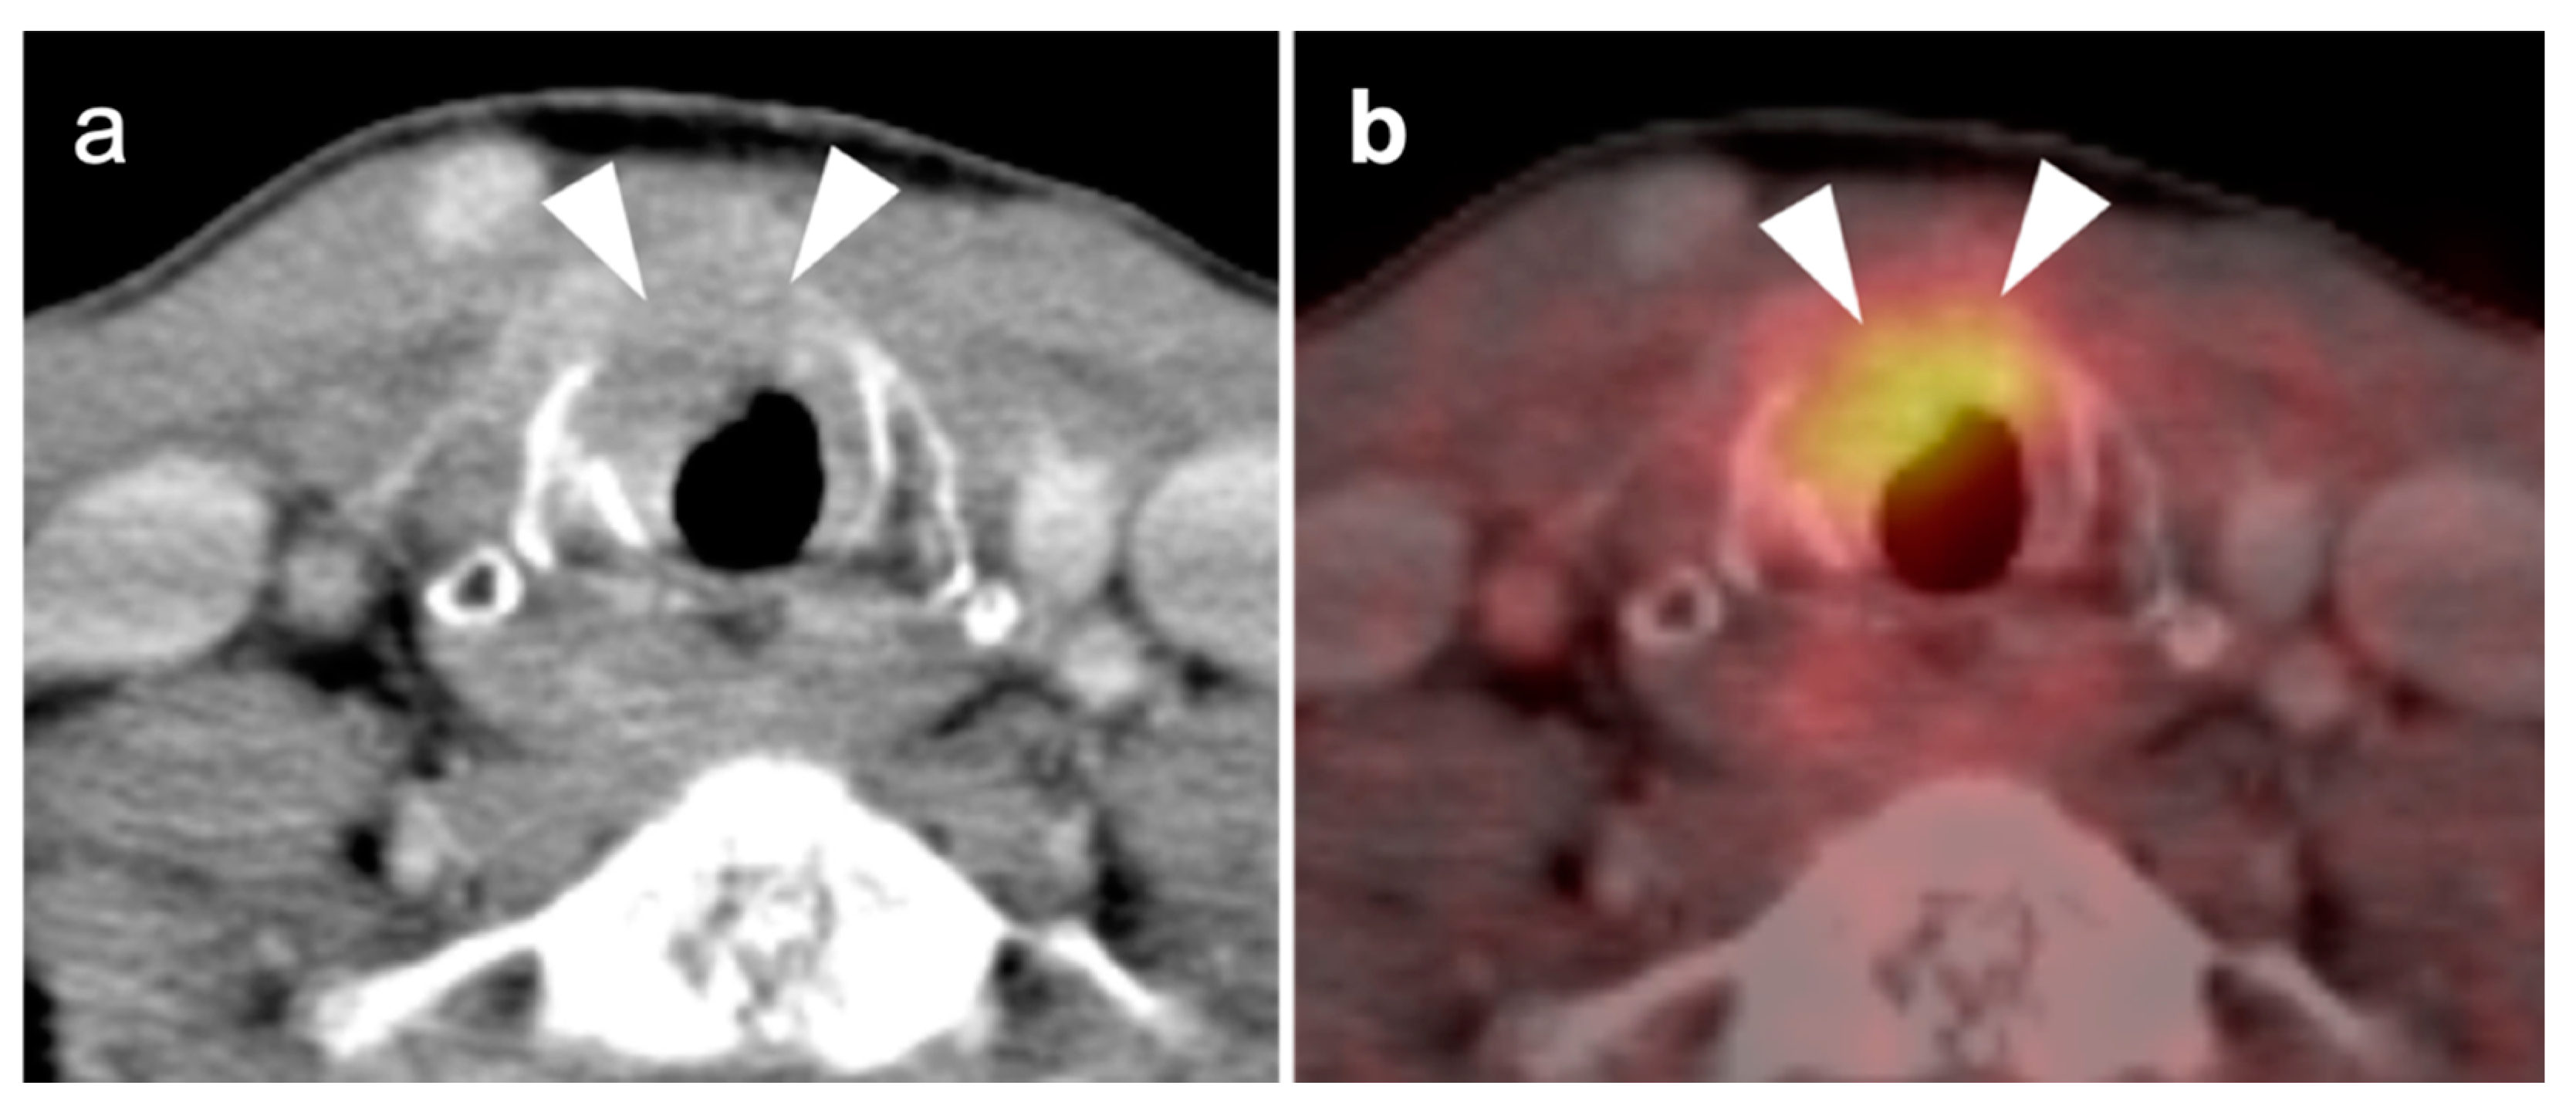

- Anaplastic thyroid cancer

2.6. Thyroid Cancer

- 4.